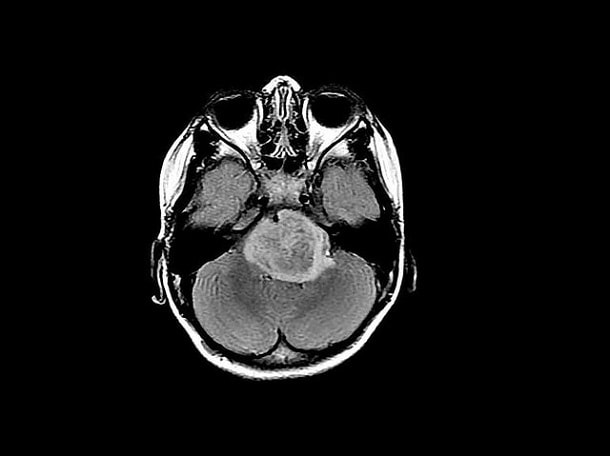

Выглядит глиома головного мозга как небольшая округлая или веретенообразная опухоль серовато-белого или темно-красного цвета диаметром от 2-3 миллиметров до размеров теннисного мяча. Растет это образование чаще медленно и характеризуется отсутствием метастазирования, но при этом развитие глиомы сопровождается дегенерацией окружающих тканей, что приводит к несоответствию размера опухоли и выраженности неврологического дефицита.

- МРТ (магнитно-резонансная томография) – один из самых информативных видов исследования. Выявляет локализацию и точный размер даже на ранних стадиях, так как предоставляет врачам картинку МРТ в трех измерениях. Метод не противопоказан во время беременности, в отличие от других видов диагностики;

- Магнитно-резонансная терапия. Это наиболее частый метод исследования, позволяющий получить контрастные изображения тканей мозга.

- МРТ. Процедура проводится практически во всех случаях, когда есть подозрения на мозговые патологии. Метод считается точным, потому как благодаря ему можно не только рассмотреть опухоль, но и уточнить её размер, место расположения и обнаружить процесс инфильтрации.